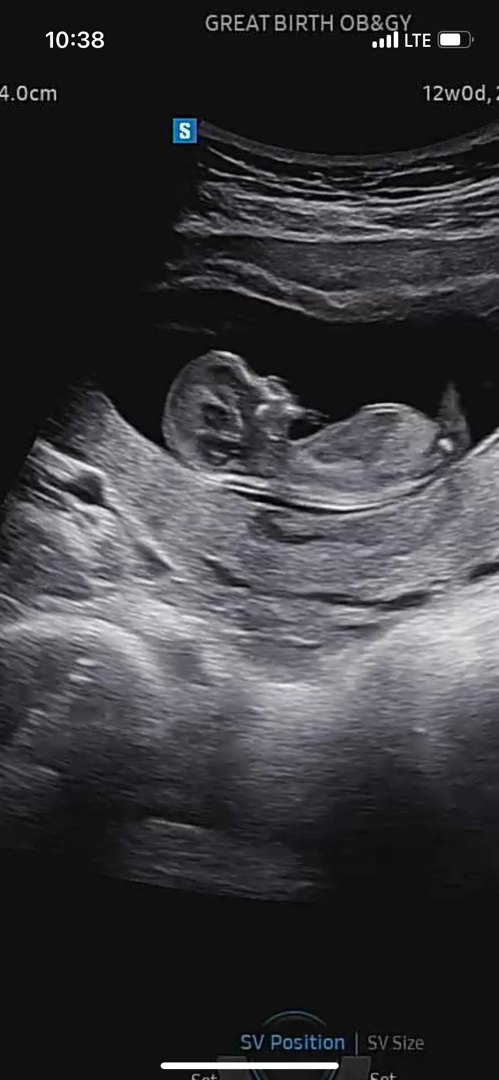

12주차 각도법 궁금합니다 ㅎㅎ

아들일까요 딸일까요? 귱금해욧